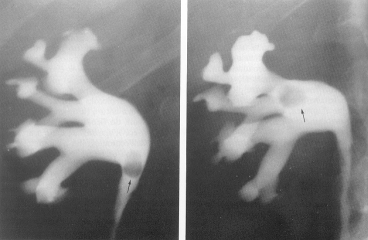

În momentul când cazeumul se elimina într-un calice mic se intra în faza deschisa a maladiei. Urina contine bacili Koch, poate fi hematurica, iar la urografia i.v. apar leziunile caracteristice

Urografia intravenoasa urmareste cu fidelitate remanierile pielo-caliciale si medulare. Cupa caliciala are contur neregulat, zdrentuit si se poate baloniza, ca urmare a stenozarii tijei caliciale corespunzatoare. Daca toate calicele mici ale unui grup calicial se dilata bulos, iar tija este îngustata apare imaginea "în margareta".